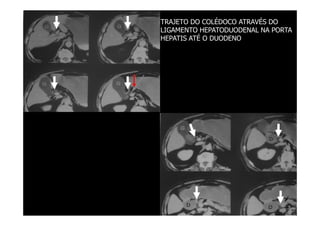

TRAJETO DO COLÉDOCO ATRAVÉS DO

LIGAMENTO HEPATODUODENAL NA PORTA

HEPATIS ATÉ O DUODENO